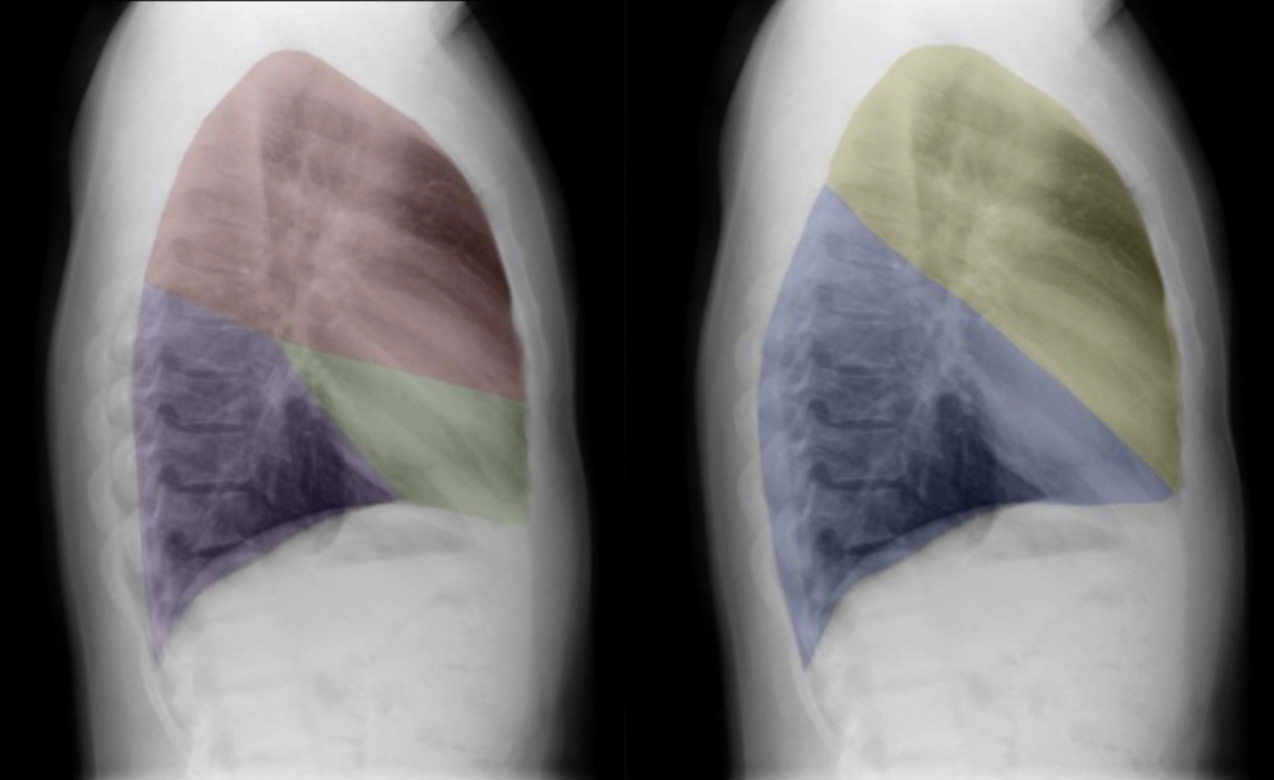

Which lobe is which ?

Red: right upper lobe (RUL)

Green: right middle lobe (RML)

Purple: right lower lobe (RLL)

Yellow: left upper lobe (LUL)

Blue: left lower lobe (LLL)

The lingular segments of the left upper lobe abut the left heart border, so can be thought of as anatomically equivalent to the middle lobe in the right lung.

“Abut” means: to lie next to or to directly touch.